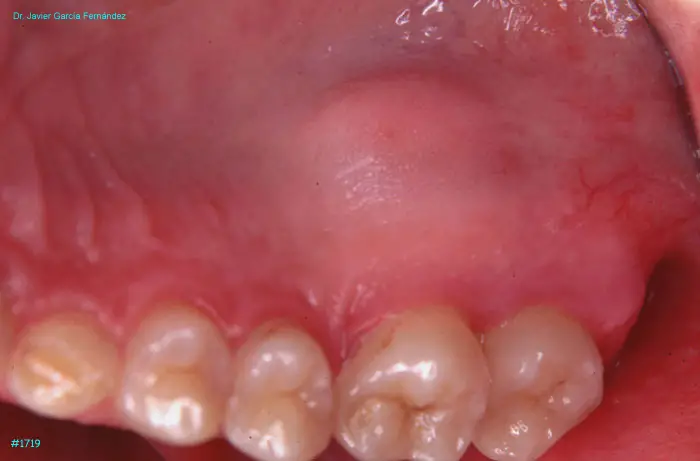

Atlas of Surgical Techniques in Periodontics. Chapter IV. Atlas de Técnicas Quirúrgica en Periodoncia

image 227